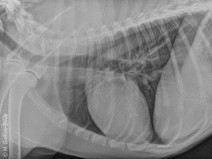

• Après-midi Travaux pratiques de radiographie / TP1 Le Thorax

Le GEIM vous propose une séance de travaux pratiques de radiographies sur le thorax. Tous les aspects sont abordés sous la forme de TP de lecture de radiographies numériques sur station de travail Osirix sur Mac (3 vétérinaires maximum/ordinateur).

Le 23 avril 2018

Mérignac (33700)

Imagerie Médicale

G.E.I.M.